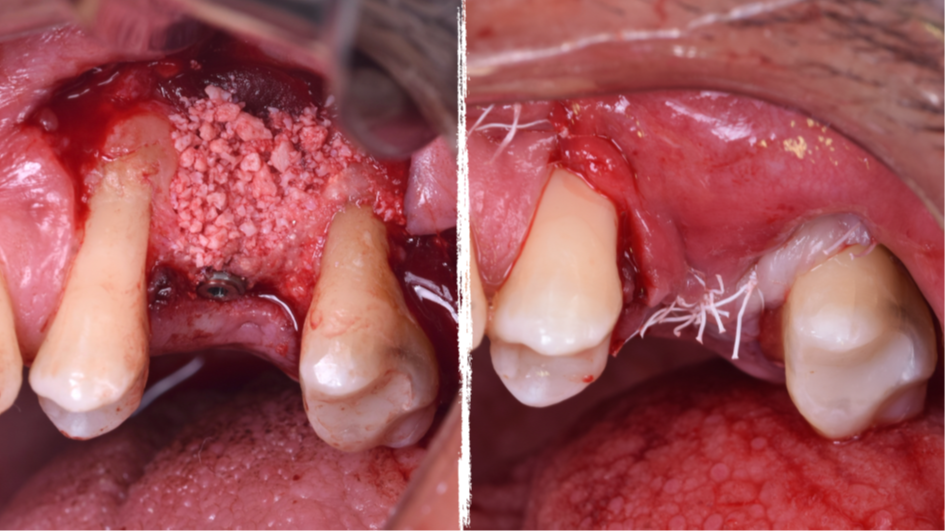

A técnica da janela lateral desenvolvida por Cadwell-Luc e modificada por Tatun na década de 1970, ainda é uma técnica previsível de sucesso para levantamentos de assoalho de seio maxilar e enxertos ósseos, pois apresenta a segurança de visualização da membrana de Schneider no processo de levantamento, quando comparada a outras técnicas de abordagem crestal.

Uma vez realizada a técnica de levantamento de seio maxilar e insucesso no ganho ósseo, a reintervenção torna-se mais complexa devido a remoção da parede vestibular e colabamento da membrana de Schneider com a mucosa vestibular.

O presente trabalho tem como objetivo fazer um relato de caso clínico de reintervenção em enxerto ósseo para levantamento de seio maxilar pela técnica da janela lateral com instalação simultânea de implante Maestro Superiore.